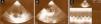

Ao 5.° dia de internamento realizou ECG e ETT (Figura 4) que mostrava o VD com dimensões normais e sem sinais de hipertensão pulmonar e ao 17.° dia teve alta medicada com enoxaparina 60mg bid sc.

Ao 30.° dia após o diagnóstico, realizou ecografia obstétrica (Figura 5) que demonstrou crescimento fetal mantido na mesma curva de percentil, morfologia, volume de líquido amniótico e fluxometria umbilical e da artéria cerebral média normais. O estudo materno de trombofilia revelou heterozigotia para o fator V de Leiden.